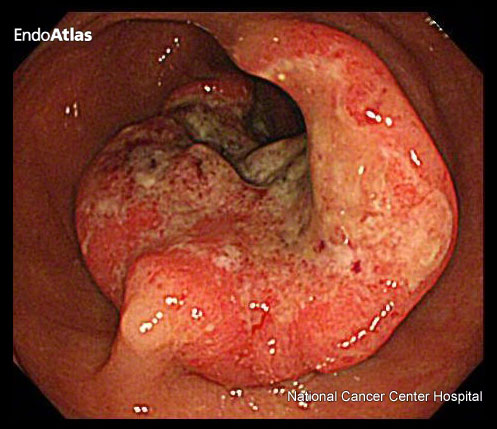

直腸がん(大腸がん)

大腸がんのなかで、肛門付近の直腸にできるがんを直腸がんといいます。

基本的には直腸の中に腫瘍はとどまりますが、進行すると肛門部まで病変が広がり、肛門部の痛みが出現する場合があります。

「長年の肛門部痛があり、痔だと思っていたら実は進行直腸がんだった」というケースもありますので、肛門部痛が続く場合には注意が必要です。